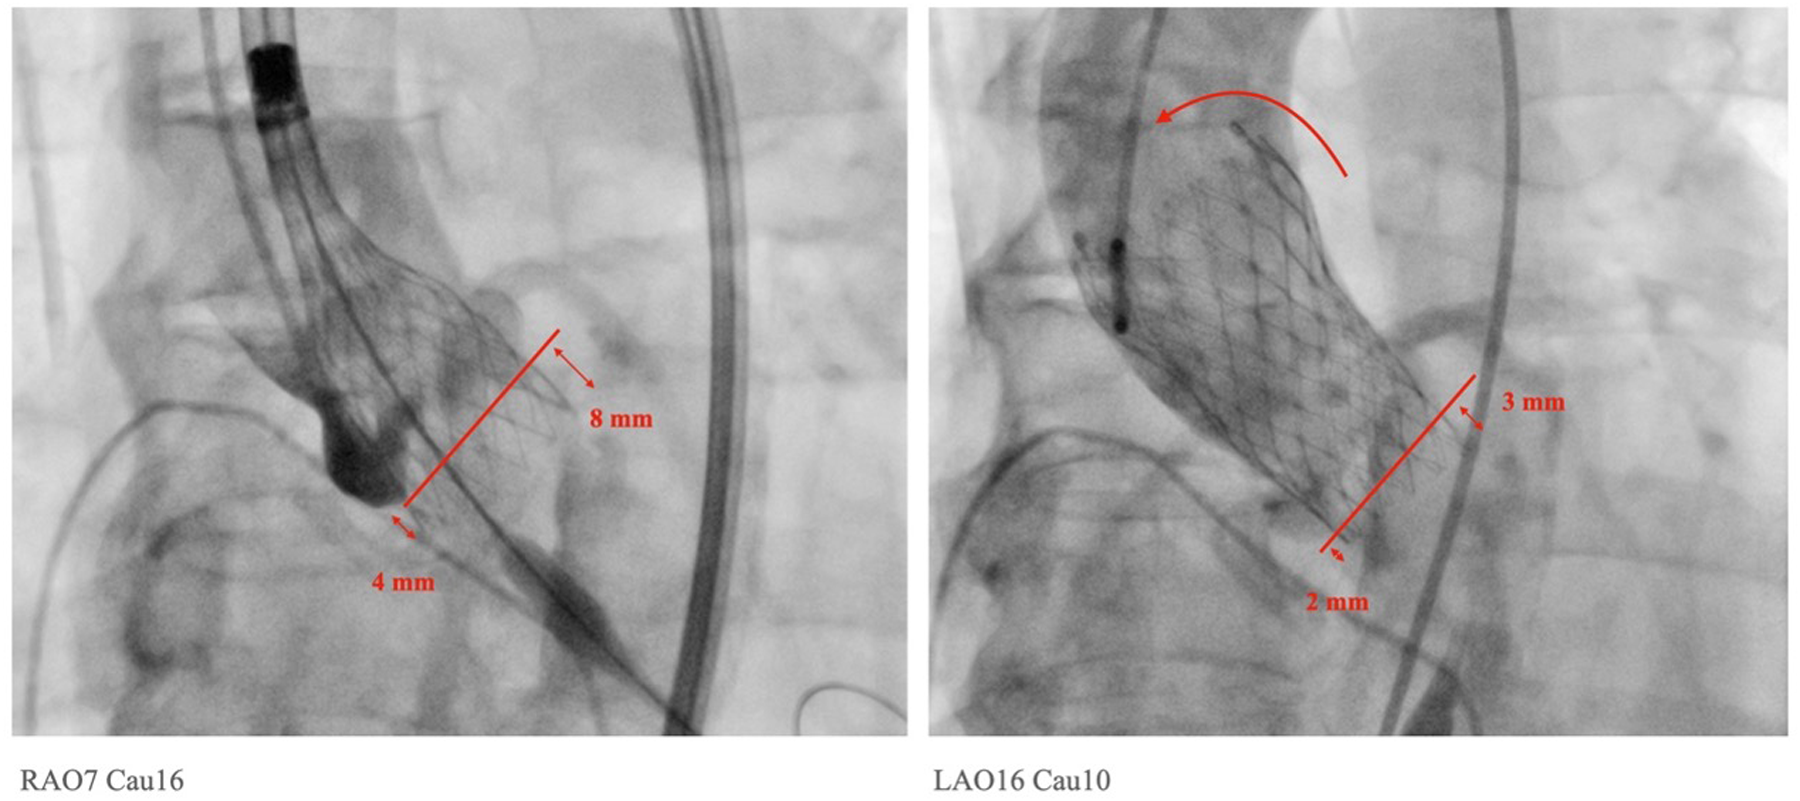

Figure 1

Measurements of implantation depth were taken in the left anterior oblique view with the removal of parallax. The implantation depths before and after final release were measured accordingly. In this particular case, a tilt of the Medtronic Evolut PRO™ with upward displacement was observed, changing from 4 mm to 2 mm on the NCC side and from 8 mm to 3 mm on the LCC side after the final release.

In contrast to the findings on the NCC side, the implantation depth below the LCC changed significantly after release. In the CON group, the depth decreased from 7.3 ± 2.8 mm in the PRD to 5.7 ± 2.3 mm after release (p < 0.0001). In the COL group, the depth decreased from 7.2 ± 2.8 mm in PRD to 4.7 ± 2.3 mm in the COL view, and to 4.6 ± 2.2 mm in the LAO parallax view (p < 0.0001). Additionally, the COL technique resulted in a significant reduction in implantation depth below the LCC after the final release (PRD: CON group vs. COL group = 7.3 ± 2.8 mm vs. 7.2 ± 2.8 mm, p = NS; RD: CON group vs. COL group = 5.7 ± 2.3 mm vs. 4.6 ± 2.2 mm, p = 0.018). These findings indicate that the SEV moved upwards significantly after release on the LCC side, while on the NCC side, there was a slight but insignificant upward displacement after the final release of the SEV. Moreover, the COL technique significantly decreases the implantation depths on both the NCC and LCC sides.